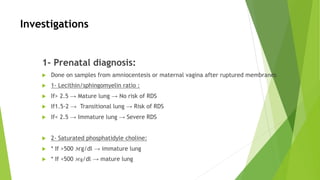

This document discusses respiratory distress and respiratory distress syndrome in neonates. It defines respiratory distress and describes the clinical signs. Various pulmonary and non-pulmonary causes are outlined. Respiratory distress syndrome, also known as hyaline membrane disease, is described in detail, including risk factors, pathophysiology, clinical presentation, investigations, complications, prevention, and treatment approaches like surfactant administration and nasal continuous positive airway pressure. The prognosis depends on gestational age and quality of care provided.